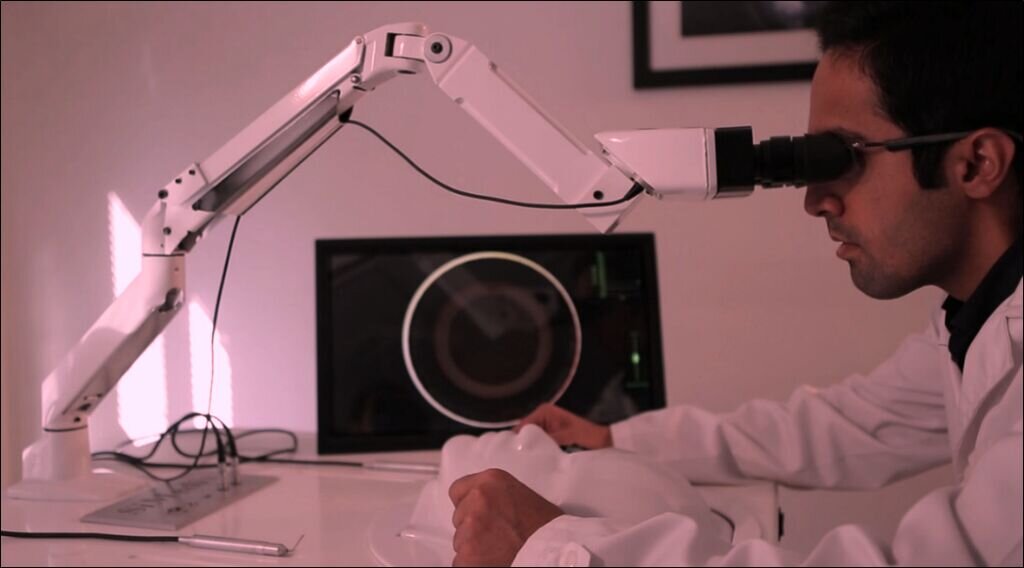

مدیرعامل یک شرکت دانشبنیان فعال در حوزه تجهیزات پزشکی درباره محصول شبیهساز آموزش جراحیهای افتالمیک (چشم) مبتنی بر واقعیت مجازی که در نمایشگاه «پیشگامان پیشرفت» حضور یافته بود به خبرنگار مهر گفت: این دستگاه، شبیهساز جراحی پزشکی است که برای آموزش جراحیهای مختلف ازجمله جراحی چشم، جراحی فک و صورت و دندانپزشکی طراحی شده است. تغییر رویکرد آموزش جراحی از بیمار واقعی به ربات و دستگاههای شبیهساز، سالهاست که در دنیا مطرح شده اما در ایران به دلیل محدودیتهای فناوری، چندان مورد توجه قرار نگرفته بود. ما از حدود ۱۰ سال پیش طراحی و ساخت این دستگاه را آغاز کردیم و طی ۵ سال اخیر، آن را به بازار معرفی کردهایم که با استقبال خوبی مواجه شده است. این شبیهساز به دانشجویان پزشکی اجازه میدهد بدون نیاز به تمرین روی بیمار واقعی، مهارتهای خود را تقویت کنند.

محمدمهدی حیدری، مدیر شرکت «آیندهنگاری همآفرینان افق»، درباره فناوری این محصول گفت: این شبیهساز مبتنی بر هوش مصنوعی و واقعیت مجازی است و با دقت بالا، بافتهای بدن انسان را شبیهسازی میکند. دانشجویان پزشکی میتوانند در محیطی کاملاً مشابه اتاق جراحی، تمرین کنند. همچنین، این دستگاه امکان دسترسی آسانتر به استاد را فراهم میکند و بخش زیادی از فرآیند آموزش را بر عهده دارد. دستگاه عملکرد دانشجویان را ارزیابی کرده و فیدبکهای لازم را ارائه میدهد. این فناوری بهویژه در دانشگاههای شهرستان که دسترسی به اساتید ممکن است محدود باشد، بسیار کاربردی است. در این شرایط، دستگاه میتواند نقش یک استاد شبیهسازیشده را با ضریب خطای بسیار پایین ایفا کند.

وی اظهار کرد؛ دستگاه شبیهساز جراحی چشم از ترکیب واقعیت مجازی و هوش مصنوعی بهره میبرد تا محیطی دقیق و تعاملی برای آموزش فراهم کند. دستگاه با شبیهسازی بافتهای بدن انسان، به دانشجویان پزشکی امکان تمرین جراحیهای پیچیده را بدون نیاز به بیمار واقعی میدهد. همچنین، با ارائه بازخورد آنی و ارزیابی عملکرد کاربر، نقش یک استاد مجازی را ایفا میکند. این فناوری نهتنها آموزش جراحی را ایمنتر و مؤثرتر کرده، بلکه با کاهش هزینهها و افزایش دسترسی، تحولی بزرگ در آموزش پزشکی ایجاد کرده است.